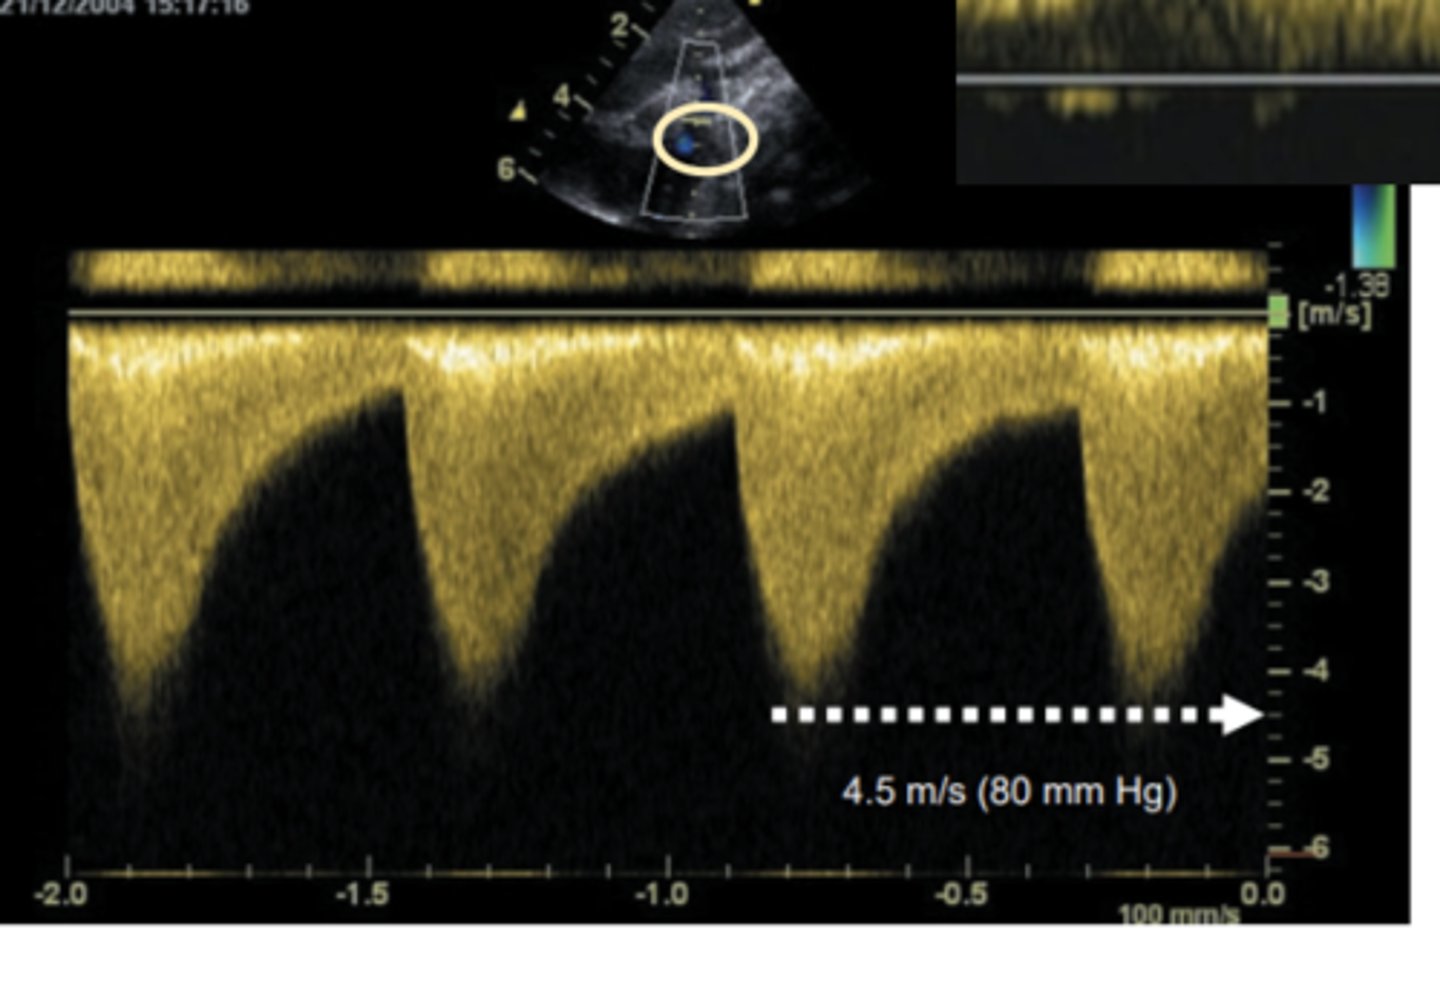

critical AS

WHAT LESION?

Interrupted Aortic Arch (IAA)